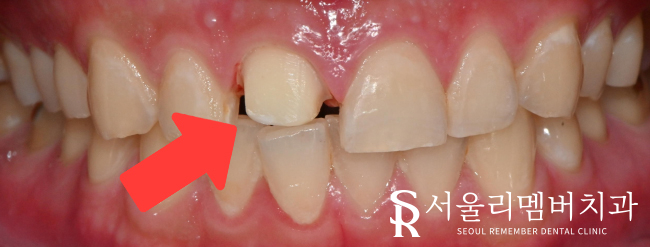

치아에 크라운을 씌울 수 있게

모양을 잡아줘야 합니다.

파절된 부분을 제거하고

매끈하게 다듬는 과정을 거쳤습니다. (prep)

보철이 제작되기 전까지는

치아를 보호하기 위해 또는 심미적인 이유로

임시치아를 제작해 드립니다.

약 일주일 후 보철물이 완성되었는데요.

사당동 치과 에서는

주변 인접치와의 형태나 모양이 조화로운지

각도나 색상은 잘 맞는지를 확인하여

크라운을 부착해 드리고

모든 과정을 마무리했습니다^^